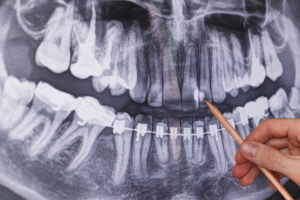

추가적인 뼈이식 비용

임플란트 시술을 위해서는 튼튼한 잇몸뼈가 필수적입니다. 하지만 나이가 들거나 치아를 상실한 지 오래된 분들의 경우 잇몸뼈가 약해져 임플란트 시술이 어려울 수 있는데요, 이러한 경우 뼈이식이 필요합니다.

뼈이식은 부족한 잇몸뼈를 보충해 임플란트가 안정적으로 자리잡을 수 있게 도와주는 과정입니다. 이 뼈이식재 또한 일종의 재료비이기 때문에, 임플란트 비용에 추가로 반영됩니다.

따라서, 잇몸뼈 상태가 좋지 않다면, 뼈이식이 필요한 만큼 비용이 더 높아질 수 있다는 점도 고려해야 합니다.